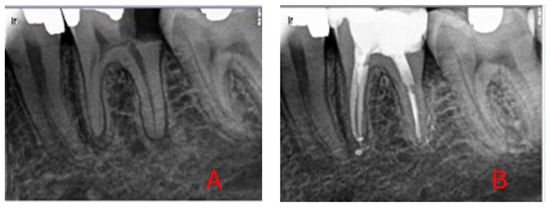

3.1. Sample Selection

3.2. Intervention Procedure